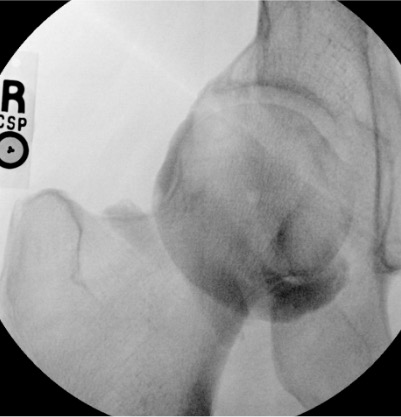

Junction of medial femoral neck and head; avoid femoral neurovascular bundle medially

12–14 mL

Intra-articular vs. extra-articular contrast distribution is the key fluoroscopic finding. Intra-articular: contrast flows freely along articular cartilage, fills joint recesses and capsular attachments. Extra-articular: contrast pools in soft tissue planes without joint recess filling — reposition needle before injecting diagnostic volume.